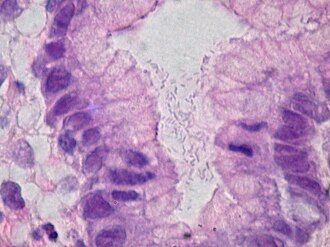

Helicobacter gastritis. H&E stain. | |

Microscopic

Features:

- Helicobacter organisms - key feature.

- Inflammation - usually moderate chronic active.

- Clusters of (lamina propria) plasma cells.

- Neutrophils, numerous, classically intraepithelial.

Tips:

- One needs to look at 400x magnification. Even at 400x they are possible to miss.

- Helicobacter are damn small. They are smaller than the nucleus of the gastric foveollar cell.

- Look for mucus - they preferentially reside there.

- This is usually close to the opening of the gastric pits.

- Helicobacter are found in groups. When you see several that are the same size and shape you can be sure they are real.